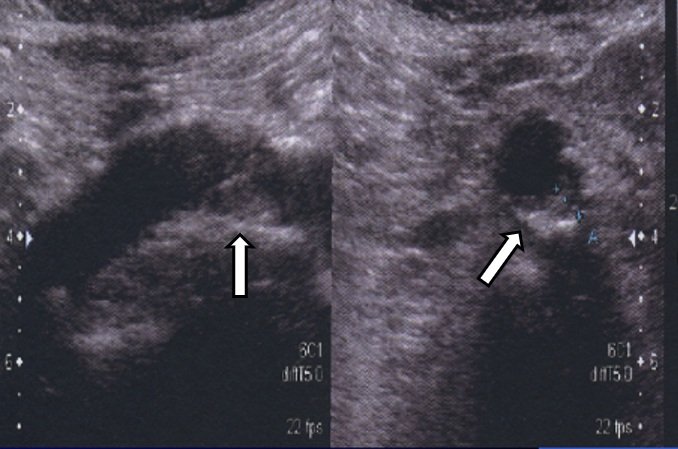

動脈は、外膜、中膜、内膜の3層で構成され、このうち内膜と中膜を合わせた厚さ(内膜中膜複合体肥厚度/IMT)を「頸動脈エコー」で測ると、動脈硬化が進行しているかどうかを知ることができ、これが全身の血管と強い関連性があることが認められています。